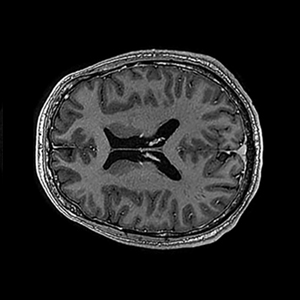

NVision, ein Ulmer Quantentechnologie-Unternehmen, hat einen sogenannten „Polarisator“ entwickelt, ein Gerät, das die Sensitivität zuckerbasierter, nicht-radioaktiver und natürlicherweise im Körper vorkommender Stoffwechselprodukte (wie beispielsweise Pyruvat) für die magnetische Detektion in einem Magnetresonanztomografen (MRT) um mehr als das 10.000-fache verstärkt. Dieser „Quanten-Zucker“, also „signalverstärkte Moleküle“, können nach der Injektion in den menschlichen Körper im Rahmen einer Standard- MRT-Bildgebung sichtbar gemacht werden.

Bisher konnten MRTs nur anatomische Informationen auf Gewebeebene liefern, aber keine Stoffwechselinformationen auf Zellebene. Das schränkt das Verständnis vieler Krankheiten, einschließlich Krebs, sehr ein. Schließlich treten Stoffwechselveränderungen in Tumoren viel früher als anatomische Veränderungen (wie bspw. Veränderungen der Tumorgröße) auf. Durch die NVision-Plattform lassen sich Stoffwechselveränderungen schnell und präzise erkennen und analysieren. „Das ermöglicht eine wesentlich verbesserte Wirksamkeitsabschätzung einer Krebsbehandlung als das in der Vergangenheit möglich war: Auf der Grundlage bisheriger Standard-MRT-Protokolle ist sie erst nach Monaten, mit der NVison-Plattform wäre sie nun innerhalb weniger Tage möglich“, so NVision-CEO Sella Brosh, M.D.